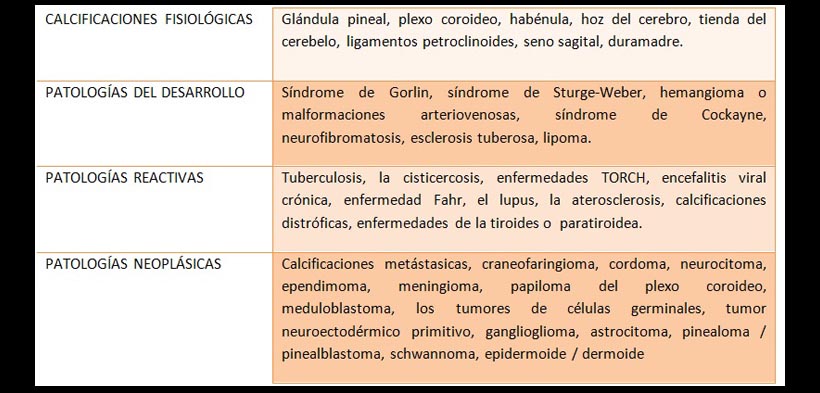

Las calcificaciones intracraneales pueden ser fisiológicas o patológicas, a menudo debido al depósito de mineral (por ejemplo el calcio) o depósito de metal (por ejemplo el hierro) en los vasos sanguíneos, glándulas, cortezas u otras estructuras en el cerebro, la etiología de las calcificaciones se mencionan en la tabla 1.

Tabla 1. Etiologías de las calcificaciones intracraneales: fisiológicas y patológicas.